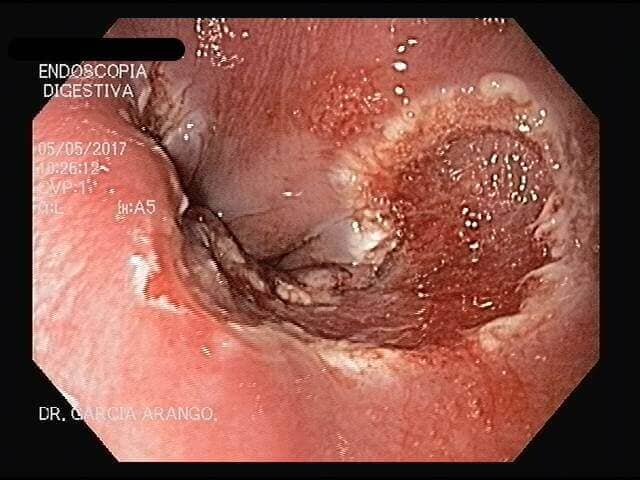

ENDOSCOPIA DIAGNÓSTICA Y TERAPÉUTICA AVANZADA CON ALTA DEFINICIÓN

⚕ Endoscopia de alta definición

⚕ Ulcera gástrica y duodenal

⚕ Detección de cáncer de tubo digestivo

⚕ Videoendoscopia y biopsias